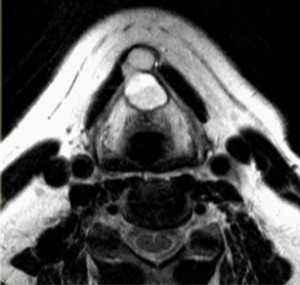

МРТ мягких тканей шеи. Т2-зависимая МРТ в аксиальной плоскости. Невринома.

Невриномы также располагаются между крупными сосудами, отодвигая их. Опухоль округлая, с четким контуром, хорошо контрастируется и в отличие от параганглиомы не содержит сосудистых включений.